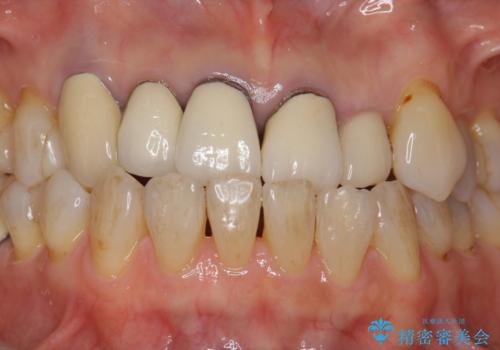

また、左上犬歯の詰め物は途中で脱離し、セラミックでの修復をご希望されたため、一緒に治療しました。

根の治療を行い、ぐらつきに関しては様子を見て連結をするとのお話をさせていただきました。

結果ナイトガードの使用によりぐらつきはだいぶ回復してきたため連結はしていません。

- 81.4万円 内訳:ジルコニアクラウン(スタンダード)11万円×4本 /精密根管治療 前歯、イニシャル 6万円×3本 /ファイバーコア 2万円×3本 /仮歯 1万円×3本/フラットタイプナイトガード 3万円費用は治療当時の料金となります